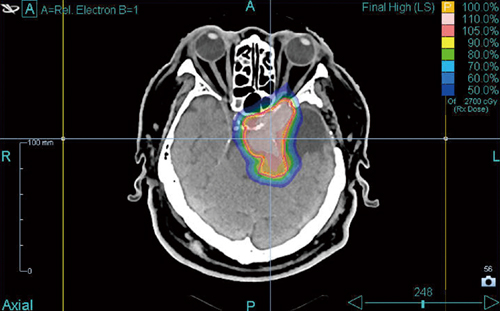

図2 症例:多発転移性脳腫瘍

近在している腫瘍は同時に照射を行う。